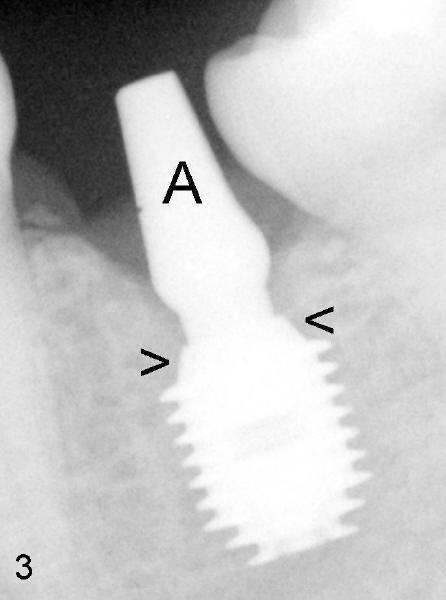

A premolar band (B in Fig.5) was cemented to the temporary crown of #19. In another two months, the tooth #18 was pushed to desired position (arrowhead) under the tension of open coil spring (*). The mesial crest height of #18 was increased during uprighting (arrow, as compared to Fig.3). Return to main article